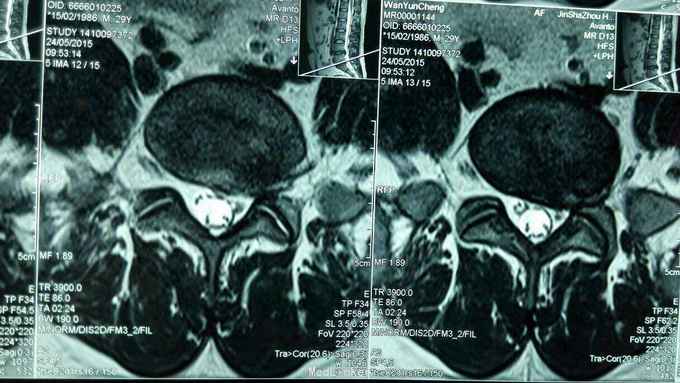

反复腰痛5年,再发5月,加重3天。 5年来反复出现腰部酸痛,未正规治疗,5个月前因腰痛不能下床,双下肢麻木,在针灸康复科住院治疗,疼痛减轻,出院休养,3天前再发腰痛,不能平躺,右下肢麻木入院。

步态正常,右侧椎间、椎旁压痛,右侧坐骨神经行程压痛,向下肢后缘放射,右侧髌腱反射、跟腱反射减弱,肌力正常。

腰椎间盘突出症,骶管囊肿 在神经阻滞麻醉下行,后路腰4~5椎间盘摘除术,骶管囊肿切开引流,神经根外膜松解术。 术后患者腰痛,右下肢麻木缓解。